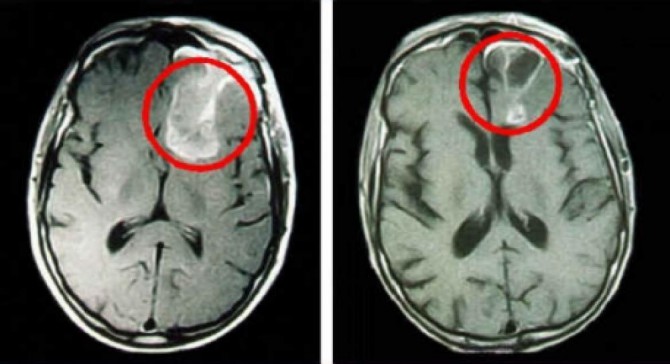

З урахуванням розташування пухлини додатково може застосовуватися комп’ютерна, магнітно-резонансна томографія, рентгенографія, ультразвукове дослідження ретроперитонеальної зони, грудини, шийної області. Якщо є припущення, що пухлина дала віддалені метастази, вдаються до радіоізотопної сцинтиграфії кісткового апарату, ультразвуку печінки, біопсії мозкових тканин, кісткового мозку, шкіри і т. п.